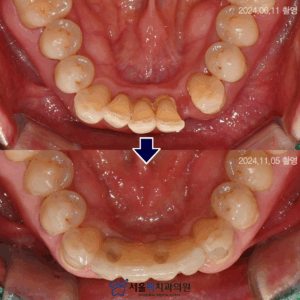

등촌동치과 앞니에 생긴 치경부우식을 레진으로 심미성을 회복하기 위해!   안녕하세요! 서울맥치과입니다:)   치과에 내원하시는 이유 중에서 가장 많이 말씀하시는 것은 아무래도 ‘충치’라고 말하는 치아우식증을 들 수 있습니다.   치아우식증은 남녀노소를 불문하고 발병률이 높은데요.   주로 음식을 저작하는 어금니의 교합면과 치아사이에 발생한다고 생각하시지만 여러원인으로 인해 ‘치경부’라는 위치에 진행되기도 하는데요.   많은 더보기…